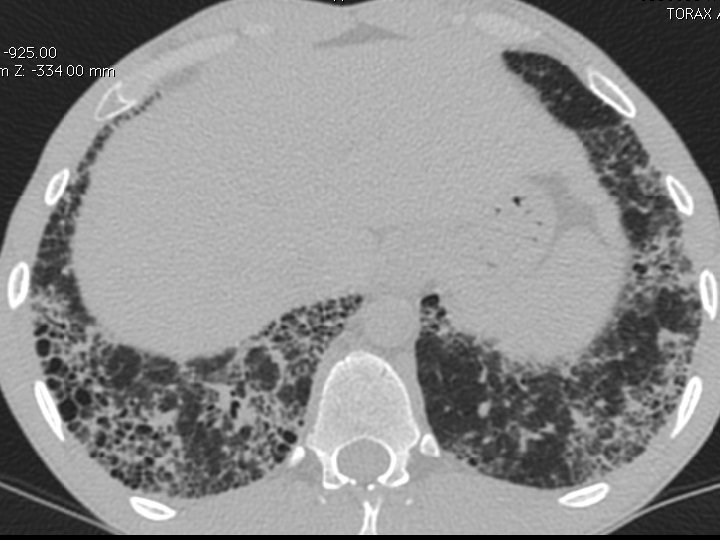

High-resolution CT scan

Subpleural, basal predominance Reticular abnormality Honeycombing with traction bronchiectasis UIPUIP Pattern

Subpleural, basal predominance Reticular abnormality Honeycombing with traction bronchiectasis Profuse micronodules UIPUIP Pattern Inconsistent with UIP Pattern

39 yo caucasian male, works in car collision repair and painting Multiple allergies, Gastroesophageal reflux disease and Thrombocytopenia of unknown etiology Smoker. No drugs CT: Reticular abnormality and honeycombing of subpleural basal predominance + micronodules Lung function tests: decreased diffusion capacity of the lung Blood tests: small increase of ESR and CRP; Autoimmune screening blood tests were normal BAL: normal celularity, with a mild increase in the neutrophil and eosinophil count

39 yo caucasian male, works in car collision repair and painting Multiple allergies, Gastroesophageal reflux disease and Thrombocytopenia of unknown etiology Smoker. No drugs CT: Reticular abnormality and honeycombing of subpleural basal predominance + micronodules Lung function tests: decreased diffusion capacity of the lung Blood tests: small increase of ESR and CRP; Autoimmune Screening Blood Tests were normal BAL: normal celularity, with a mild increase in the neutrophil and eosinophil count Definitive diagnosis can be established? Additional diagnostic tests required? Which tests?